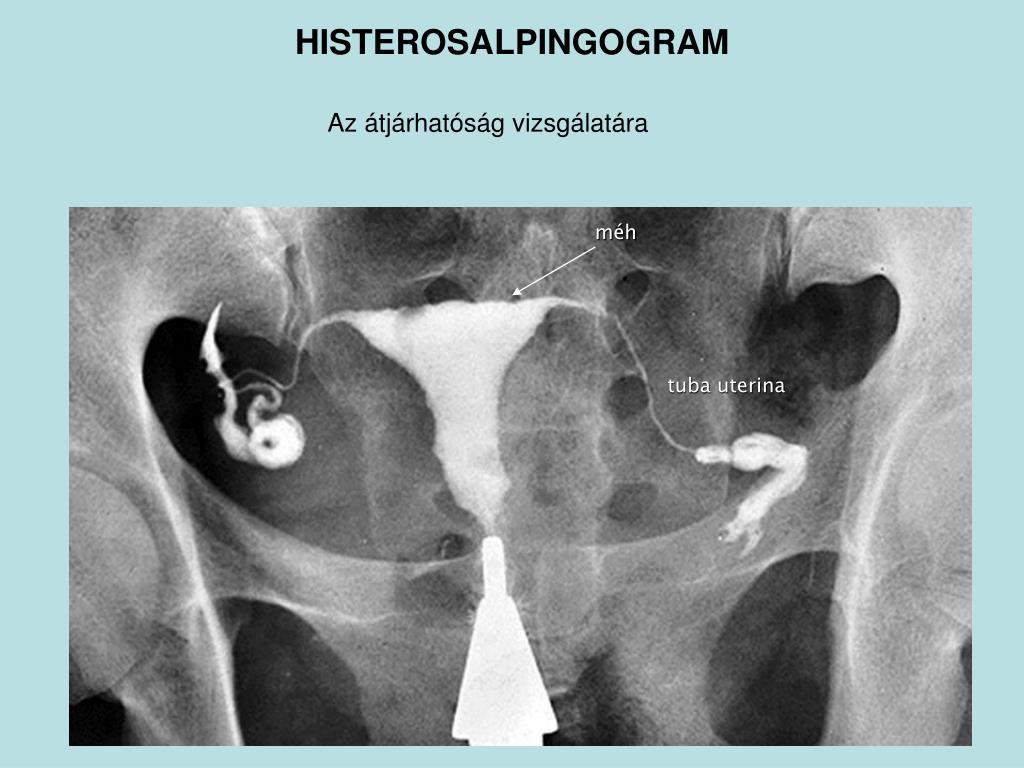

Медицинские снимки: Проходимость маточных труб

Раздел: Кадры-подсказки